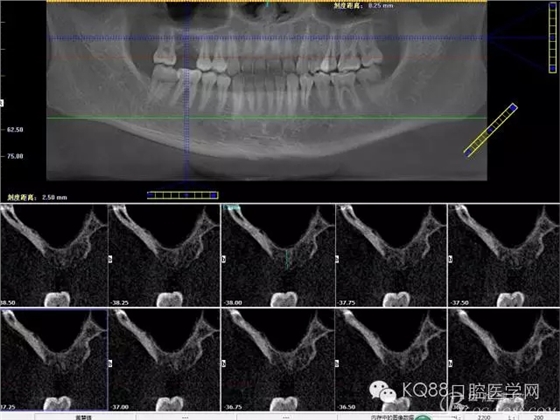

下面是拔牙后三個(gè)月的CBCT。垂直骨高度約6.7mm。

另外一個(gè)切面。垂直骨高度不夠,準(zhǔn)備 :做內(nèi)提升,植骨,植入植體。